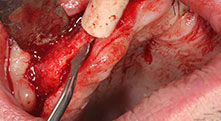

Piezomed B6

La crête alvéolaire a été clivée des deux côtés par chirurgie piézoélectrique (instrument : Piezomed B6). Les implants ont été posés lors de la même intervention et l'os péri-implantaire a été reconstitué à l'aide de la technique de GBR.